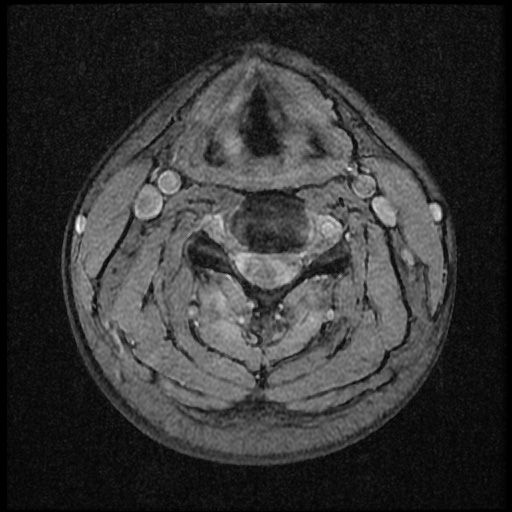

근대 21년 사고 이후부터 목쪽이 계속 아픈 상태 여서 사고로 인한 급성인지 우연이 겹친 민성 디스크 인지 확인하고 싶습니다~

이 MRI 사진은 21년도 사고 당시 찍은 MRI 사진 입니다. 확인 부탁드립니다~

전체 mri를 다 봐여겠지만 보여주신 mri 컷에서는 의미있는 경추 디스크탈출이 보이지 않습니다.